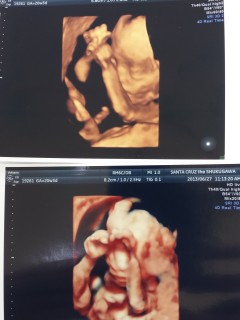

初めての4Dエコー!微笑みながらスヤスヤ寝てました(*´ー`)輪郭やお鼻、耳が既に旦那さんに似ているように見えました!性別は女の子とのことです。